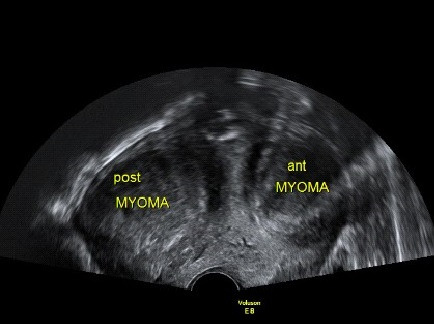

아래는 임신을 준비하는 여성들의 초음파 검사에서 관찰되는 영상입니다.

자궁근종이 있는지, 자궁 용종이 있는지, 난소에 혹이 있는지 확인할 수 있는 간편하면서도 정확도가 높은 검사입니다. 비용은 병원마다 천차만별이오니 꼭 미리 확인하고 가시기 바랍니다. 자궁근종, 자궁 용종, 난소에 자궁내막종의 여부에 따라 난임에 대한 접근방법이 바뀔 수 있어 필수적으로 시행하는 검사입니다.

여성 생식기를 보게 되며, 보는 방법에는 질식 초음파와 복식 초음파, 음순을 이용한 초음파 방법이 있습니다만, 가장 많이 이용하는 방법은 복식 초음파(Transabdominal USG)와 질식 초음파(Transvaginal USG)입니다. 쉽게 설명하면, 산모의 태아를 보듯 배를 통해서 보면 복식 초음파이고, 질(vagina), 아기가 나오는 길(산도)을 통해서 보게 되면 질식 초음파입니다.

임신하지 않은 여성이나 10~12주 이전 산모의 경우에는 태아가 작아서 질식 초음파를 이용해서 태아를 관찰하는 경우가 많습니다. 그리고 20주 이후에도 자궁경부를 확인하기 위해서 질식 초음파를 관찰할 때가 있습니다.

일반 여성 환자의 경우, 복부 초음파로 검사를 시행할 수도 있지만, 하복부 지방으로 인해서 복식 초음파가 쉽지 않을 때가 많고, 질식 초음파가 훨씬 선명하기에 질식 초음파를 사용하게 됩니다.